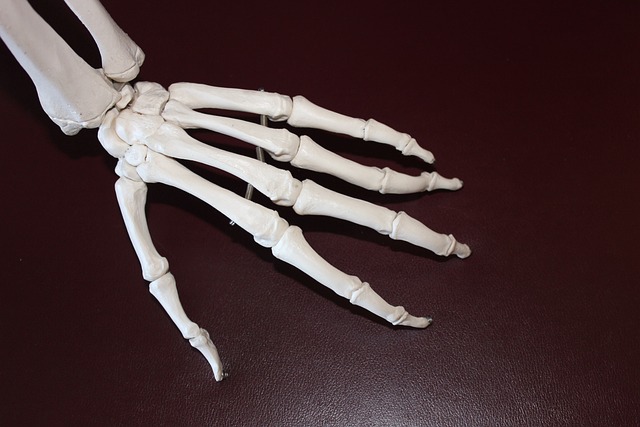

퇴행성 관절염은 관절의 연골이 서서히 손상되어 발생하는 만성적인 질환으로, 주로 노인이나 중년에 많이 발생합니다.

□ 나이 : 나이가 들면서 뼈와 관절의 건강이 악화되는 것은 피할 수 없는 현상입니다. 이는 퇴행성 관절염의 주요 위험 요인 중 하나 입니다.